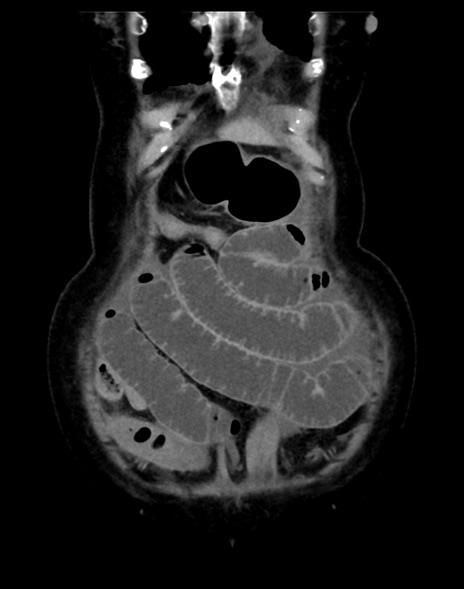

(横断像)1日半後